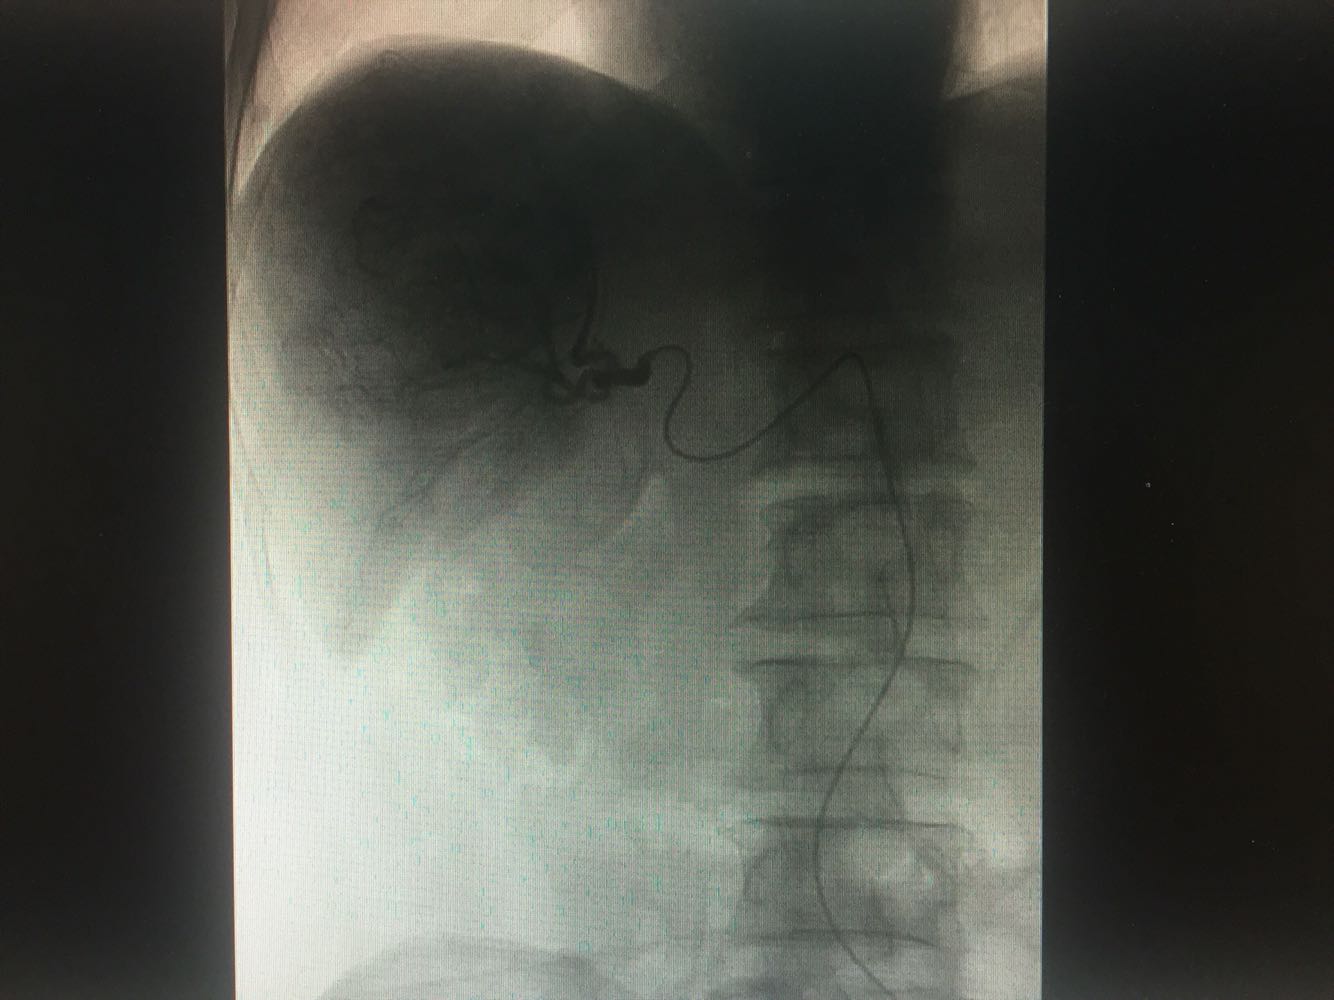

查体:体温,36摄氏度,脉搏:60次/分,呼吸,19次/分、血压,115/70mmhg,发育正常,营养欠佳,皮肤黏膜,色泽正常,双侧眼睑正常,双侧巩膜无黄染,口唇红润,双肺呼吸音清晰,心率60次/分,心律齐,心音有力,无病理性杂音。右上腹部饱满,中上腹压痛明显,肝脏肋下2cm触及,质地硬,触痛阳性,脾肋下2cm触及,移动性浊音阴性,肠音正常,双下肢无水肿 化验:血常规:白细胞计数2.9*10~9/L,中性粒细胞1.4*10~9L,红细胞计数4.03*10^12L,血小板计数76*10^9/L;生化全套。血糖4.67mol/L,总蛋白81.0g/L,白蛋白40.9g/1L,丙氯酸氨基转移酶256U/L,天门冬氨酸氨基转移酶182U,总胆红素22.0umol/L,胆碱酯酶4479U/L,Y-谷氨酰基转移酶137U/L;传染病9项:乙型肝炎病表面抗原阳性/6380,乙型肝炎病毒e抗体阳性/0.004,乙型肝炎病毒核心抗体阳性/0.008 肿瘤标志物:甲胎蛋白415.50ng/ml,乙型肝炎病毒DNA测定2.06E+07IU/ml CT:1.考虑肝右叶巨块型肝癌伴肝内多发转移,2.肝门部及腹膜后、心隔角旁小淋巴结。3.肝小囊肿。4.肝左叶増大。5.肝脏钙化灶。6.副牌。7.双肾微小囊肿

乙肝肝硬化,原发性肝癌,保肝抗病毒治疗,及TACE

出院一月后复查,行增强CT扫描,肿瘤明显缩小,肝功能正常,乙肝病毒复制转阴,建议继续口服恩替卡韦抗病毒治疗